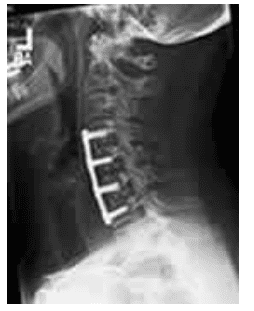

4.2.2 Phẫu thuật giải ép lối trước

Phẫu thuật giải ép lối trước giúp loại bỏ trực tiếp gai xương và thoát vị đĩa đệm chèn ép tủy, ghép xương. Một số trường hợp, tiến đến đặt nẹp vít hàn xương giúp ngăn ngừa mất vững cột sống cổ sau mổ.

Phẫu thuật giải ép và đặt dụng cụ hàn xương lối trước

Lựa chọn đường mổ phía trước hay sau phụ thuộc nhiều yếu tố khác nhau nhưng mục tiêu trước hết là phải mở rộng ống sống đủ để giải ép tủy. Và trước khi mổ, phải loại trừ bệnh lý tủy cổ không phải do thoái hóa như bệnh xơ cứng rải rác, xơ cứng cột bên teo cơ.